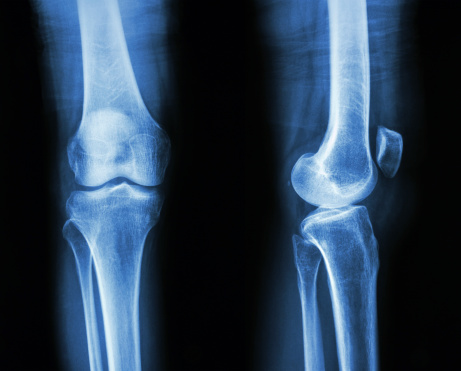

성장판의 위치. 사진=게티이미지뱅크

성장판이란 다리 뼈에서 가운데 부분과 양끝 부분의 사이에 남아 있는 연골조직으로 골의 길이 성장이 일어나는 부분이다.

성장판은 대개 뼈의 양쪽 끝에 있으며, 뼈와 뼈 사이에 연골판이 끼어 있는 형태로 있다. 태아 때에 팔다리뼈는 모두 연골로 되어 있고, 태아가 성장하면서 연골의 한가운데 부분이 뼈로 바뀌면서 양쪽 끝으로 점차 퍼져나가게 된다. 이 부분을 일차 골화중심이라고 한다.

한편 팔다리 뼈의 양쪽 끝에 아직 뼈로 바뀌지 않은 연골 부위에 자체적으로 또 뼈로 바뀌는 부분이 나타나는데, 이를 이차 골화중심이라고 한다.

이렇게 뼈의 가운데와 양쪽 끝에서 연골이 뼈로 점차 바뀌고 그 사이에 남은 연골 부분이 성장판이 된다. 그러다가 사춘기쯤 되면 성장판도 모두 뼈로 바뀌게 되면서 길이 성장이 끝나게 된다.

성장판은 태생기부터 작동하며 성장이 멈추는 시기는 부위마다 닫히는 시기가 제각각이다. 여자는 약 15세, 남자는 약 17세가 되면 모든 성장판이 닫히면서 더 이상 키가 자라지 않는다. 그러나 개인적인 차이가 약간 있을 수 있으며, 특정한 병적인 상태에서는 보다 빨리 또는 늦게 성장판이 닫히는 경우도 있다.